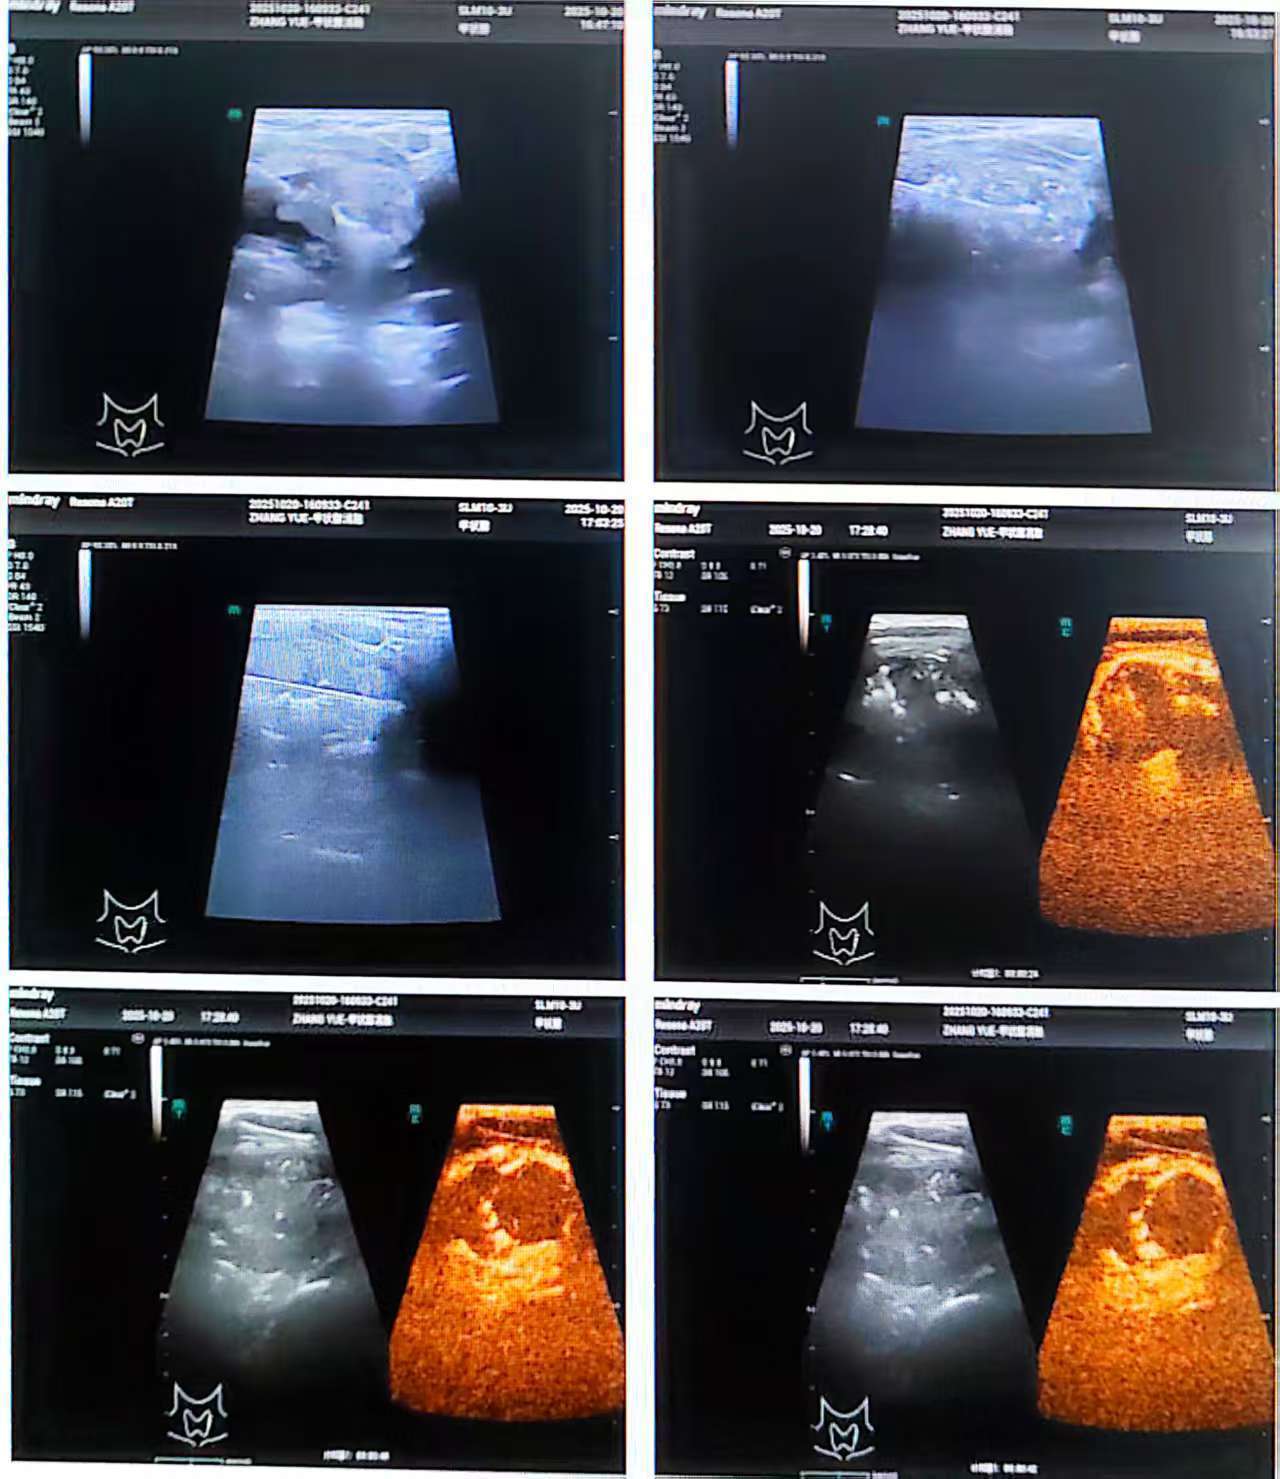

张永东主任启动多学科协作(MDT)诊疗流程,邀请病理科杨巧医生共同会诊。在超声引导下,张主任精准完成穿刺取样,杨巧医生随即运用 ROSE 技术,于手术床旁即刻完成细胞学诊断,确认结节为良性。

征得患者同意后,张永东主任在同一穿刺点实施甲状腺射频消融术,治疗后患者颈部仅留下微不可见的针眼,数日后完全愈合,既消除了健康隐患,又保障了颈部美观。